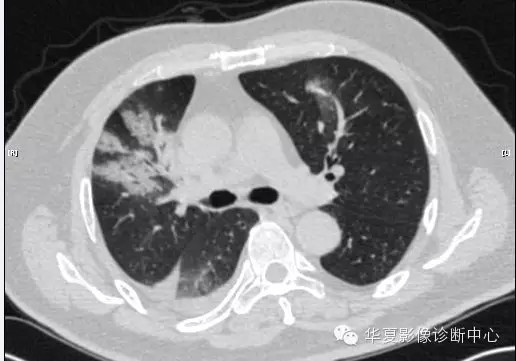

【病例学习】甲型H7N9禽流感一例

男性 63

发热咳嗽5天

2013-4-5拍片示右肺实变,收入院,追问病史,发病期间肌肉酸痛,头痛,无腹痛腹泻,无明显胸闷气急,无意识改变。有高血压病史,无其它病史。

2013-4-7CT进一步检查。

最终诊断:H7N9。